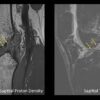

One of the largest MRI-based studies comparing knee injuries between men and women reveals surprising differences in injury patterns based on gender and age. The findings can be used to improve risk assessment and develop early intervention strategies. The study included 13,549 consecutive routine knee MRI exams performed between 2019 and 2024 at...